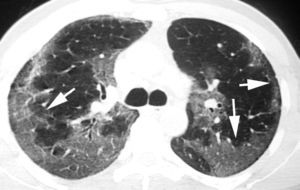

En algunos casos de NINE, como suele suceder en otras neumonías intersticiales, la radiografía de tórax es normal27,28. En la TCAR, lo que caracteriza al patrón de NINE es el «vidrio deslustrado» periférico, en las zonas medias y basales de ambos pulmones (fig. 8)29,30. La panalización ocurre en el 27% de los pacientes, y a medida que progresa la fibrosis, las bronquiectasias y bronquiolectasias de tracción son más visibles7,31. Los hallazgos radiológicos pueden desaparecer por completo tras el tratamiento con esteroides.

El estudio radiológico es normal en el 22% de los pacientes con NID34. La imagen TCAR consiste en opacidades bilaterales en «vidrio deslustrado» de localización simétrica y basal (fig. 9). También se han descrito opacidades lineales y reticulares que en ocasiones son indistinguibles de los hallazgos radiológicos descritos en la NIU35,36.